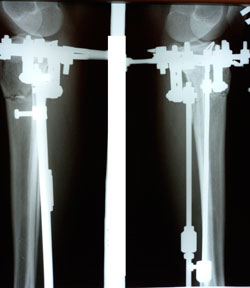

Дата операции - 28.01.2021

Исходник - 42 года.

5 ый день после операции

дата снятия аппаратов - 17.06.2021